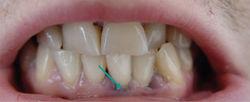

鉛線——為鉛中毒特徵性體徵。

鉛中毒在口腔里的特徵性表現是:沿著牙齦乳頭邊緣上發生一條約1mm 的藍灰色或藍黑色“鉛線”,口腔不清潔的人這條鉛線特別明顯。這種色素也可以發生在口腔局部黏膜上形成較大的鉛斑。